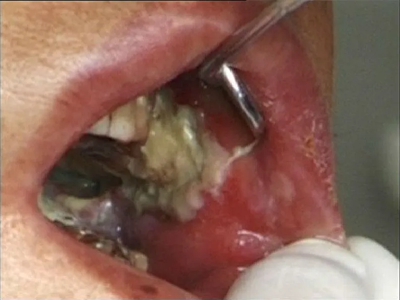

口腔

肿块

颊癌口腔黏膜长肿块表面发白出血图

颊癌发生在口腔内的颊黏膜靠近牙齿的部位,由许多颗粒状肉芽凸起融合成肿块,上附有白膜,看起来凹凸不平,并有出血现象,应及时手术切除,并辅以化疗及放疗。